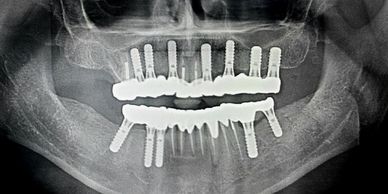

Screw-Retained Retrievable Prosthetics For maximum longevity and maintenance ease, we specialize in screw-retained prosthetic solutions. These allow for future adjustments, professional cleaning, and component replacement without compromising the implant foundation.

Our premium zirconia crowns and bridges offer superior aesthetics and unmatched durability. These biocompatible restorations resist staining, wear, and fracture while maintaining a natural appearance that complements your smile.